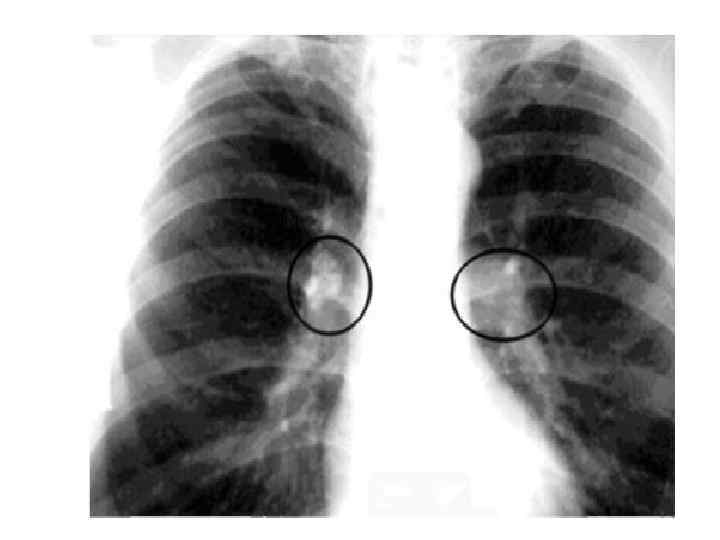

Варианты течения ТВГЛУ 1) с неосложнённым течением, 2) с осложнённым течением. • Клиническая картина неосложнённого ТВЛУ характеризуется симптомами интоксикации и наблюдается в современных условиях у 85% больных (В. А. Соколов). Рентгенологическая картина обусловлена изменениями корней лёгких, реже – средостения, при вовлечении в процесс нескольких групп ВЛУ. • Клиническая и рентгенологическая картина осложнённого ТВЛУ, характеризуется вовлечением в процесс бронхов, плевры, лёгких.